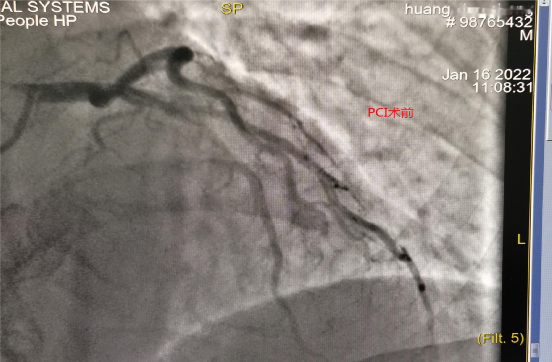

医生边询问病史边行床边心电图,并上传到胸痛中心微信群。拨打胸痛中心一键启动电话行远程会诊,经会诊后确诊STEMI(前壁),建议排除禁忌后,予第三代溶栓药瑞通立全量静注溶栓治疗。医疗救治、辅助检查、医患沟通紧张有序进行,确诊10分钟内予负荷量双抗血小板、稳定斑块治疗,并联系120转胸痛中心治疗。在诊治过程中,患者突然意识丧失,呼之不应,抽搐、小便失禁,心电监护示室颤,考虑心脏骤停,立即予心脏按压、呼吸囊辅助通气、双向波200J电除颤、静注肾上腺素等抢救治疗,约4分钟后患者恢复窦性心律,颈动脉可触及搏动,恢复自主呼吸,血压90/50mmHg,有溶栓禁忌症,边抢救边转送到总院人民医院胸痛中心治疗。通过区域协同救治机制,院内院外搭建绿色通道,绕开急诊科及CCU病房,直达介入室予PCI治疗,术中见前降支中段狭窄>90%,向前TIMI血流2级,11:08导丝通过,予植入支架1枚。患者住院治疗5天,病情稳定,未出现并发症,康复出院。